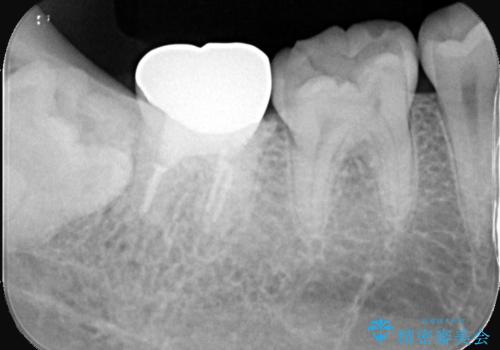

- 「銀歯を白くしたい」を主訴に来院された患者様です。

銀歯と虫歯を除去後、オールセラミッククラウンで治療を行いました。

銀歯を除去後、オールセラミッククラウンで治療を行いました。

根管治療はご希望されなかったため被せ物のみ治療しています。

クリアランスが少なかったため支台歯の真ん中に保持溝を入れています。